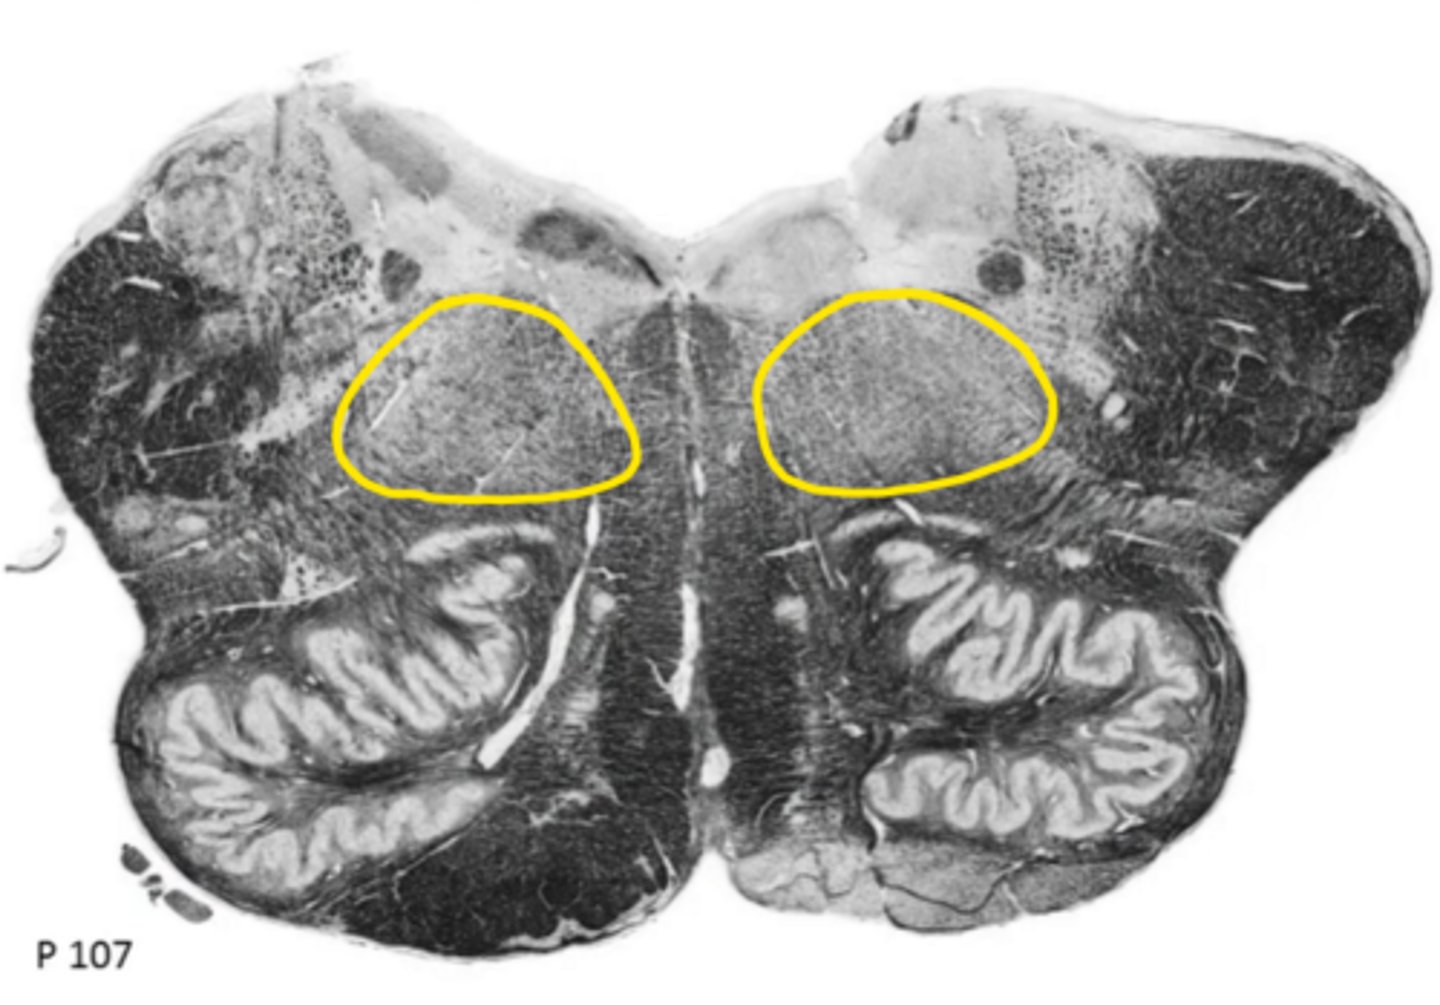

open medulla

ID the brainstem level